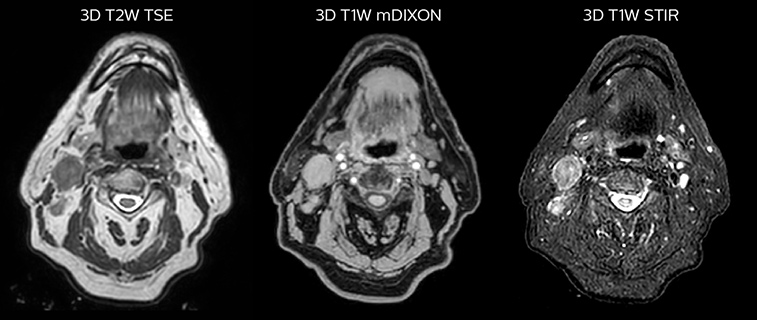

While CT clearly defines bone and cartilage, the modality’s limited soft tissue visualization makes head-and-neck structures often appear virtually indistinguishable from another. Coregistering an MRI dataset as a secondary information source for head-and-neck target and organ at risk (OAR) delineation is vital, according to La Tour’s Dr. Breuneval.

“MRI contributes substantially to visualizing head-and-neck lesions compared to CT and allows a better differentiation of normal from abnormal tissue,” he explains. “Tumor edges and extracapsular lymph node extension – as well as OARs, such as parotid glands, pharyngeal muscles and the brachial plexus – are better depicted. The resulting benefit is that tumor margins may be reduced and OARs better spared.”

Comparison of CT simulation scan (left) and T2W 3D MRI (right)